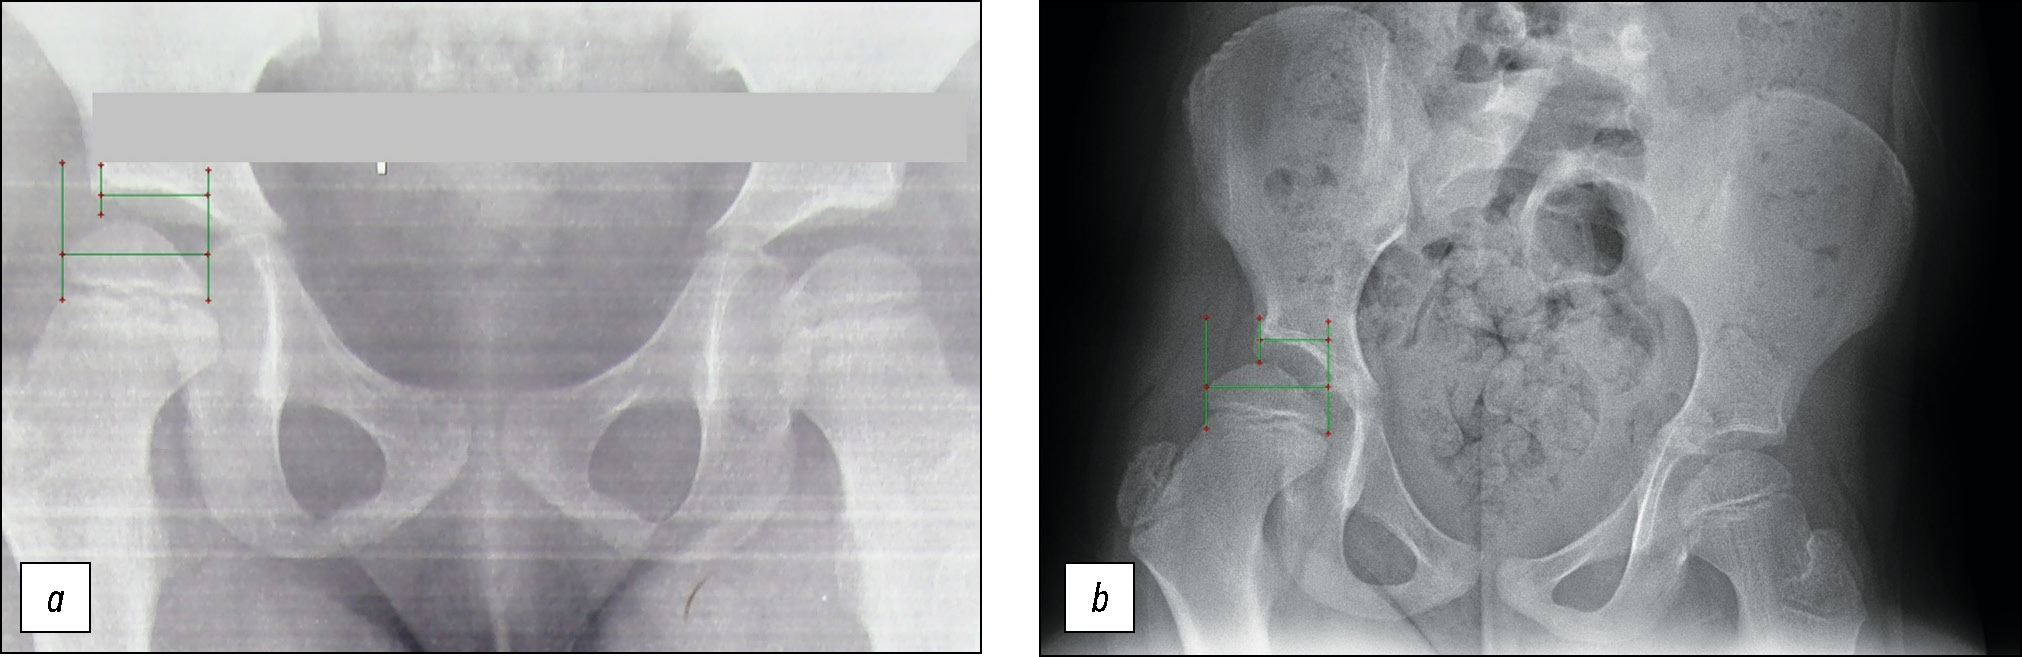

Так, на представленных рентгенограммах, выполненных в положении лёжа и в положении стоя, отмечается изменение покрытия головки бедра крышей вертлужной впадины. Коэффициент покрытия головки бедра в положении лёжа составляет 0,74 (рис. 1а), в то время как на постуральных рентгенограммах в положении стоя у этого же пациента данный коэффициент уменьшается и составляет 0,56 (рис. 1b). Такие изменения расценены нами как позиционный подвывих головки бедра, который обусловлен тем, что головка бедра более длинной нижней конечности при нагрузке уходит в положение подвывиха за счёт наклона таза в сторону более короткой ноги, происходит приведение в тазобедренном суставе и смещение вектора опоры.

Рис. 1. Пациентка П., 8 лет. Диагноз: дисплазия тазобедренных суставов. Неравенство длины нижних конечностей. а — прямая рентгенограмма таза, коэффициент покрытия головки бедра составляет 0,74; b — постуральная рентгенограмма нижних конечностей, коэффициент покрытия головки бедра составляет 0,56.

Fig. 1. Patient Р., 8 y.o. Congenital hip dysplasia. а — anterior-posterior radiography of the pelvis, head coverage ratio is 0.74; b — full-length postural radiography of the lower extremities, head coverage ratio is 0.56.

Формирование позиционного подвывиха в положении стоя выявлено у 8 пациентов с удлинением конечности на стороне скомпрометированного тазобедренного сустава. В среднем при удлинении сегмента на 1 см и более коэффициент покрытия головки бедра уменьшался на 10% в положении стоя, что указывало на увеличение нестабильности сустава при нагрузке.